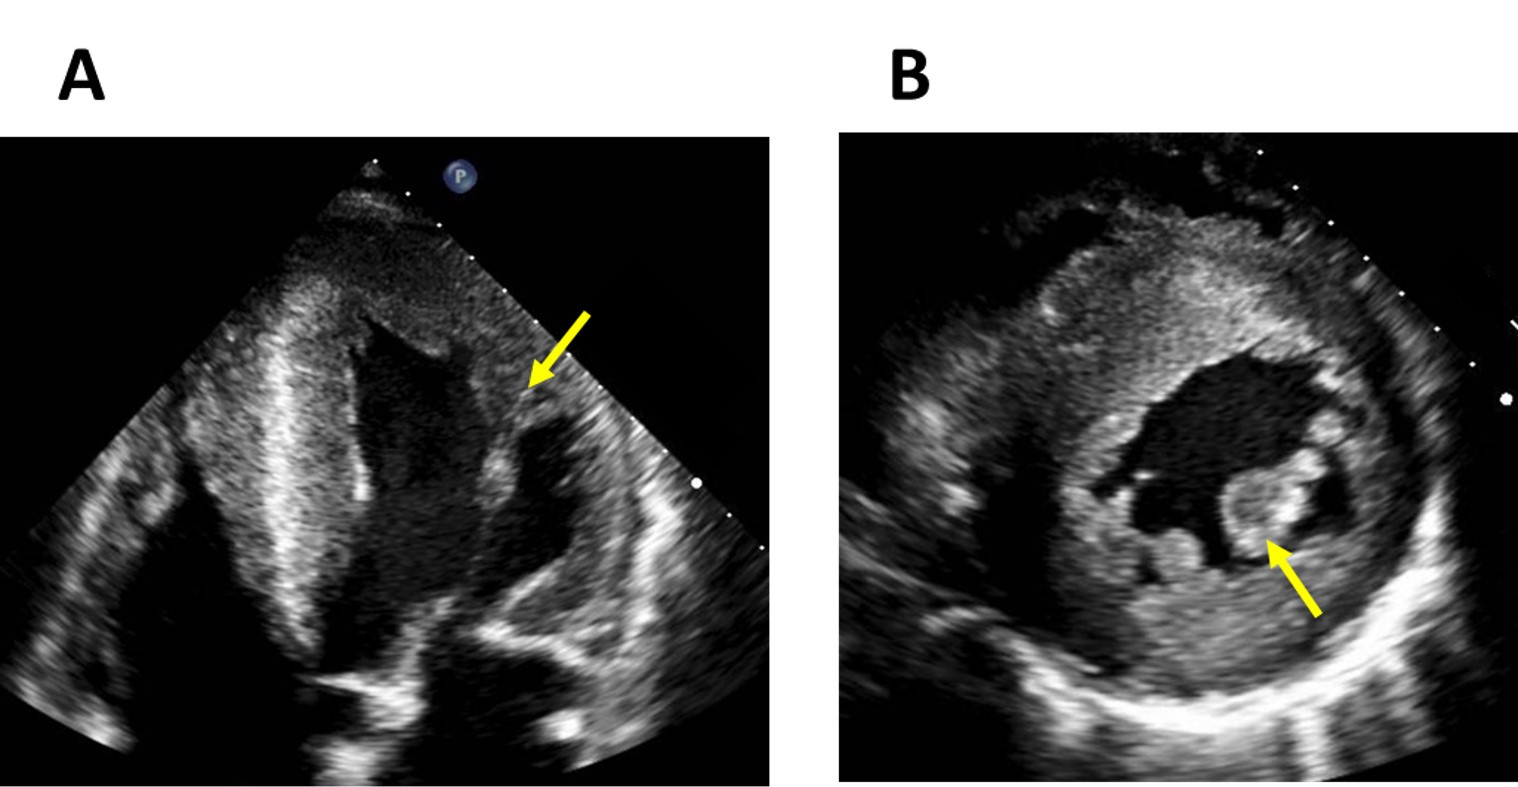

LVH in FD typically presents a concentric pattern (Fig. 2) without resting left ventricular outflow tract obstruction (LVOTO). However, obstructive forms, asymmetric septal (Fig. 3), apical and eccentric hypertrophy have also been described [19, 20]. In fact, LVOTO may be more prevalent and have a greater impact on symptoms than was previously thought. In a small cohort of 14 patients, LVOTO was revealed by exercise stress echocardiography in six patients with refractory symptoms [21]. A smaller cavity size and papillary muscle (PM) hypertrophy were speculated to be involved in the LVOTO.

Fig. 2.Left ventricular and papillary muscle hypertrophy in Fabry disease. Echocardiography four-chamber view (A) and short-axis CMR image (B) that shows a severe left ventricular hypertrophy and papillary muscle hypertrophy (arrows) in a 47-year-old male patient with Fabry disease.

Disproportionate hypertrophy of PM could also be a useful marker of FD (Fig. 2).

Niemann et al. [22] showed that PM area (measured by echocardiography in

the mid-ventricular short axis view) and the ratio of PM area to the

circumference of the left ventricle (LV) were significantly higher in FD patients

compared to patients with other diseases that cause LVH (amyloidosis, aortic

stenosis, hypertrophic cardiomyopathy (HCM), etc.) with a cut-off value of 3.6

cm